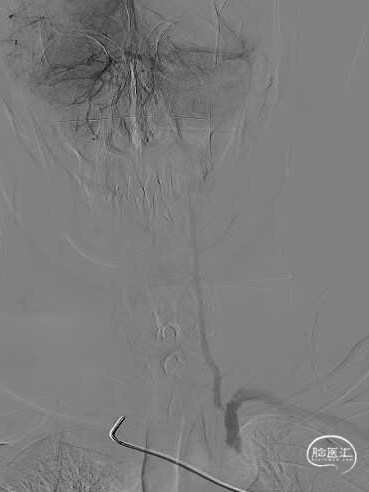

右侧椎动脉造影提示左侧锁骨下动脉盗血,左侧锁骨下动脉闭塞,近端残端较圆钝。

8F Guiding+5F MPA同轴置于左侧锁骨下动脉残端处,反复尝试Command 190cm及Command ES 190cm导丝配合Rebar-18微导管,导丝无法进入真腔,更换Connect 195cm导丝尝试后顺利进入真腔,使用小球囊预扩, Guiding跟到病变远端。

更换Supracore导丝,使用雅培 5*40mm Armada35 球囊扩张后在闭塞起始部植入8*29mm Omnilink支架。

使用雅培 Command导丝顺利超选进入左椎V2段,冠脉3.0*12mm球囊进行扩张,在V18导丝的支撑下,在左侧椎动脉起始部植入一枚雅培4.5*15mm Herculink支架。支架植入后,造影提示椎动脉狭窄得到明显改善。